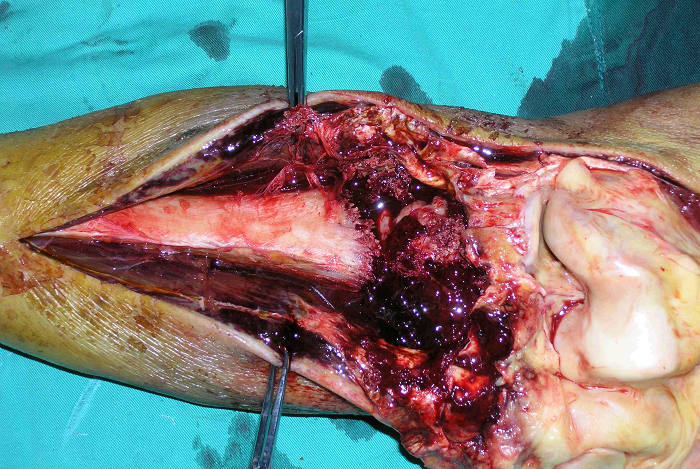

5、病例5:男 65岁 左胫骨上段毛细血管扩张性骨肉瘤,因活检术后持续性出血,行大腿中段截肢术

图 26术前X线片

a:正位 b:侧位

图 27 6周后病变范围显著扩大

图 28 术前CT横断面象

图 29 术前CT冠状面象

图 30 患肢外观

图 31 肿瘤病灶外观

图 32 组织学特点:在扩张的血管间

见异型成骨细胞,正常的骨小梁

被破坏。